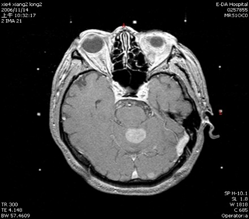

轉移性腦瘤

手術前

手術後